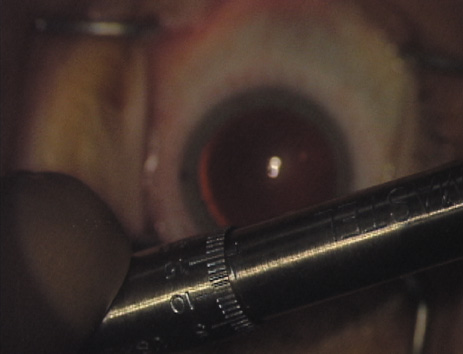

As noted, in the setting of concomitant cataract surgery, an empiric blade

depth setting of 600 microns is commonly employed. Various knives

have been designed specifically for this application, ranging from disposable

steel blades to exquisite gemstone diamond knives. Synthetic (and

less expensive) diamond materials are also available and

are intended for limited reuse. Our preference is for diamond blade technology

that incorporates a single small and arced footplate for enhanced

visualization at the limbus (Mastel Precision). Two models

are available, one with a preset depth of 600 microns and the other

with an adjustable micrometer handle (Fig. 6). Similar designs are available from Rhein Medical, Storz, ASICO, and

other manufacturers.   Fig. 6. (A)A diamond blade with a preset depth of 600 microns is used

to perform LRIs for routine cataract surgery. (B) An adjustable

depth micrometer blade is used in conjunction with the NAPA nomogram

when treating younger patients. Fig. 6. (A)A diamond blade with a preset depth of 600 microns is used

to perform LRIs for routine cataract surgery. (B) An adjustable

depth micrometer blade is used in conjunction with the NAPA nomogram

when treating younger patients.

|